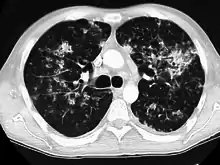

Tuberculosis of the lungs

A case of miliary tuberculosis in an 82-year-old woman: